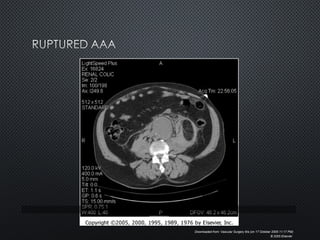

• RUPTURE IS THE GRAVEST AND MOSTRUPTURE IS THE GRAVEST AND MOST

COMMON COMPLICATIONCOMMON COMPLICATION

• RUPTURED AAA 90% MORTALITYRUPTURED AAA 90% MORTALITY